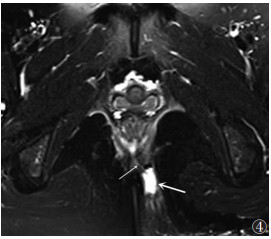

![]() |

| 图 4 男,37岁,经括约肌的复杂瘘管(Ⅳ级),轴位脂肪抑制序列T2WI显示坐骨直肠脂肪间隙脓肿(粗箭)及经内外括约肌的瘘管(细箭) |